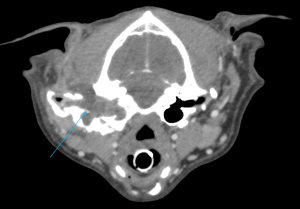

こんにちは、獣医師の依田です。 今回は、耳の根元の腫れで来院したわんちゃんの紹介です。 飼い主様が数日前から耳…]]>

こんにちは、獣医師の依田です。 今回は、耳の根元の腫れで来院したわんちゃんの紹介です。 飼い主様が数日前から耳…]]>